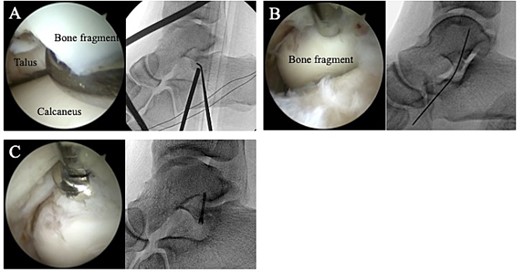

A 24-year-old male basketball player presented to our hospital complaining of left lateral ankle pain during a cutting motion. His height, weight, and body mass index were 172 cm, 64.0 kg, and 21.6 kg/m2, respectively, and he had no history of previous medical conditions. On his first visit to our hospital, he could not walk due to pain. Physical examination revealed swelling, ecchymosis, and tenderness at the lateral aspect of his left ankle. The American Orthopedic Foot and Ankle Society (AOFAS) score was 32 out of 100 points. Plain radiographs of the left ankle showed no abnormal findings in the anteroposterior view, but a fracture line was discovered at the base of the lateral process of the talus in the lateral view (Fig. 1). Non-contrast computed tomography (CT) showed a simple fracture line that extending from the talofibular articular surface down to the posterior talocalcaneal articular surface of the subtalar joint. In addition, the bone fragment was displaced >2 mm (Fig. 2). The patient was diagnosed with Type I LPFT and underwent surgical treatment.

Plain radiographs of the left ankle showed no abnormal findings in the anteroposterior (A) view, but a fracture line was discovered at the base of the lateral process of the talus in the lateral (B) view.